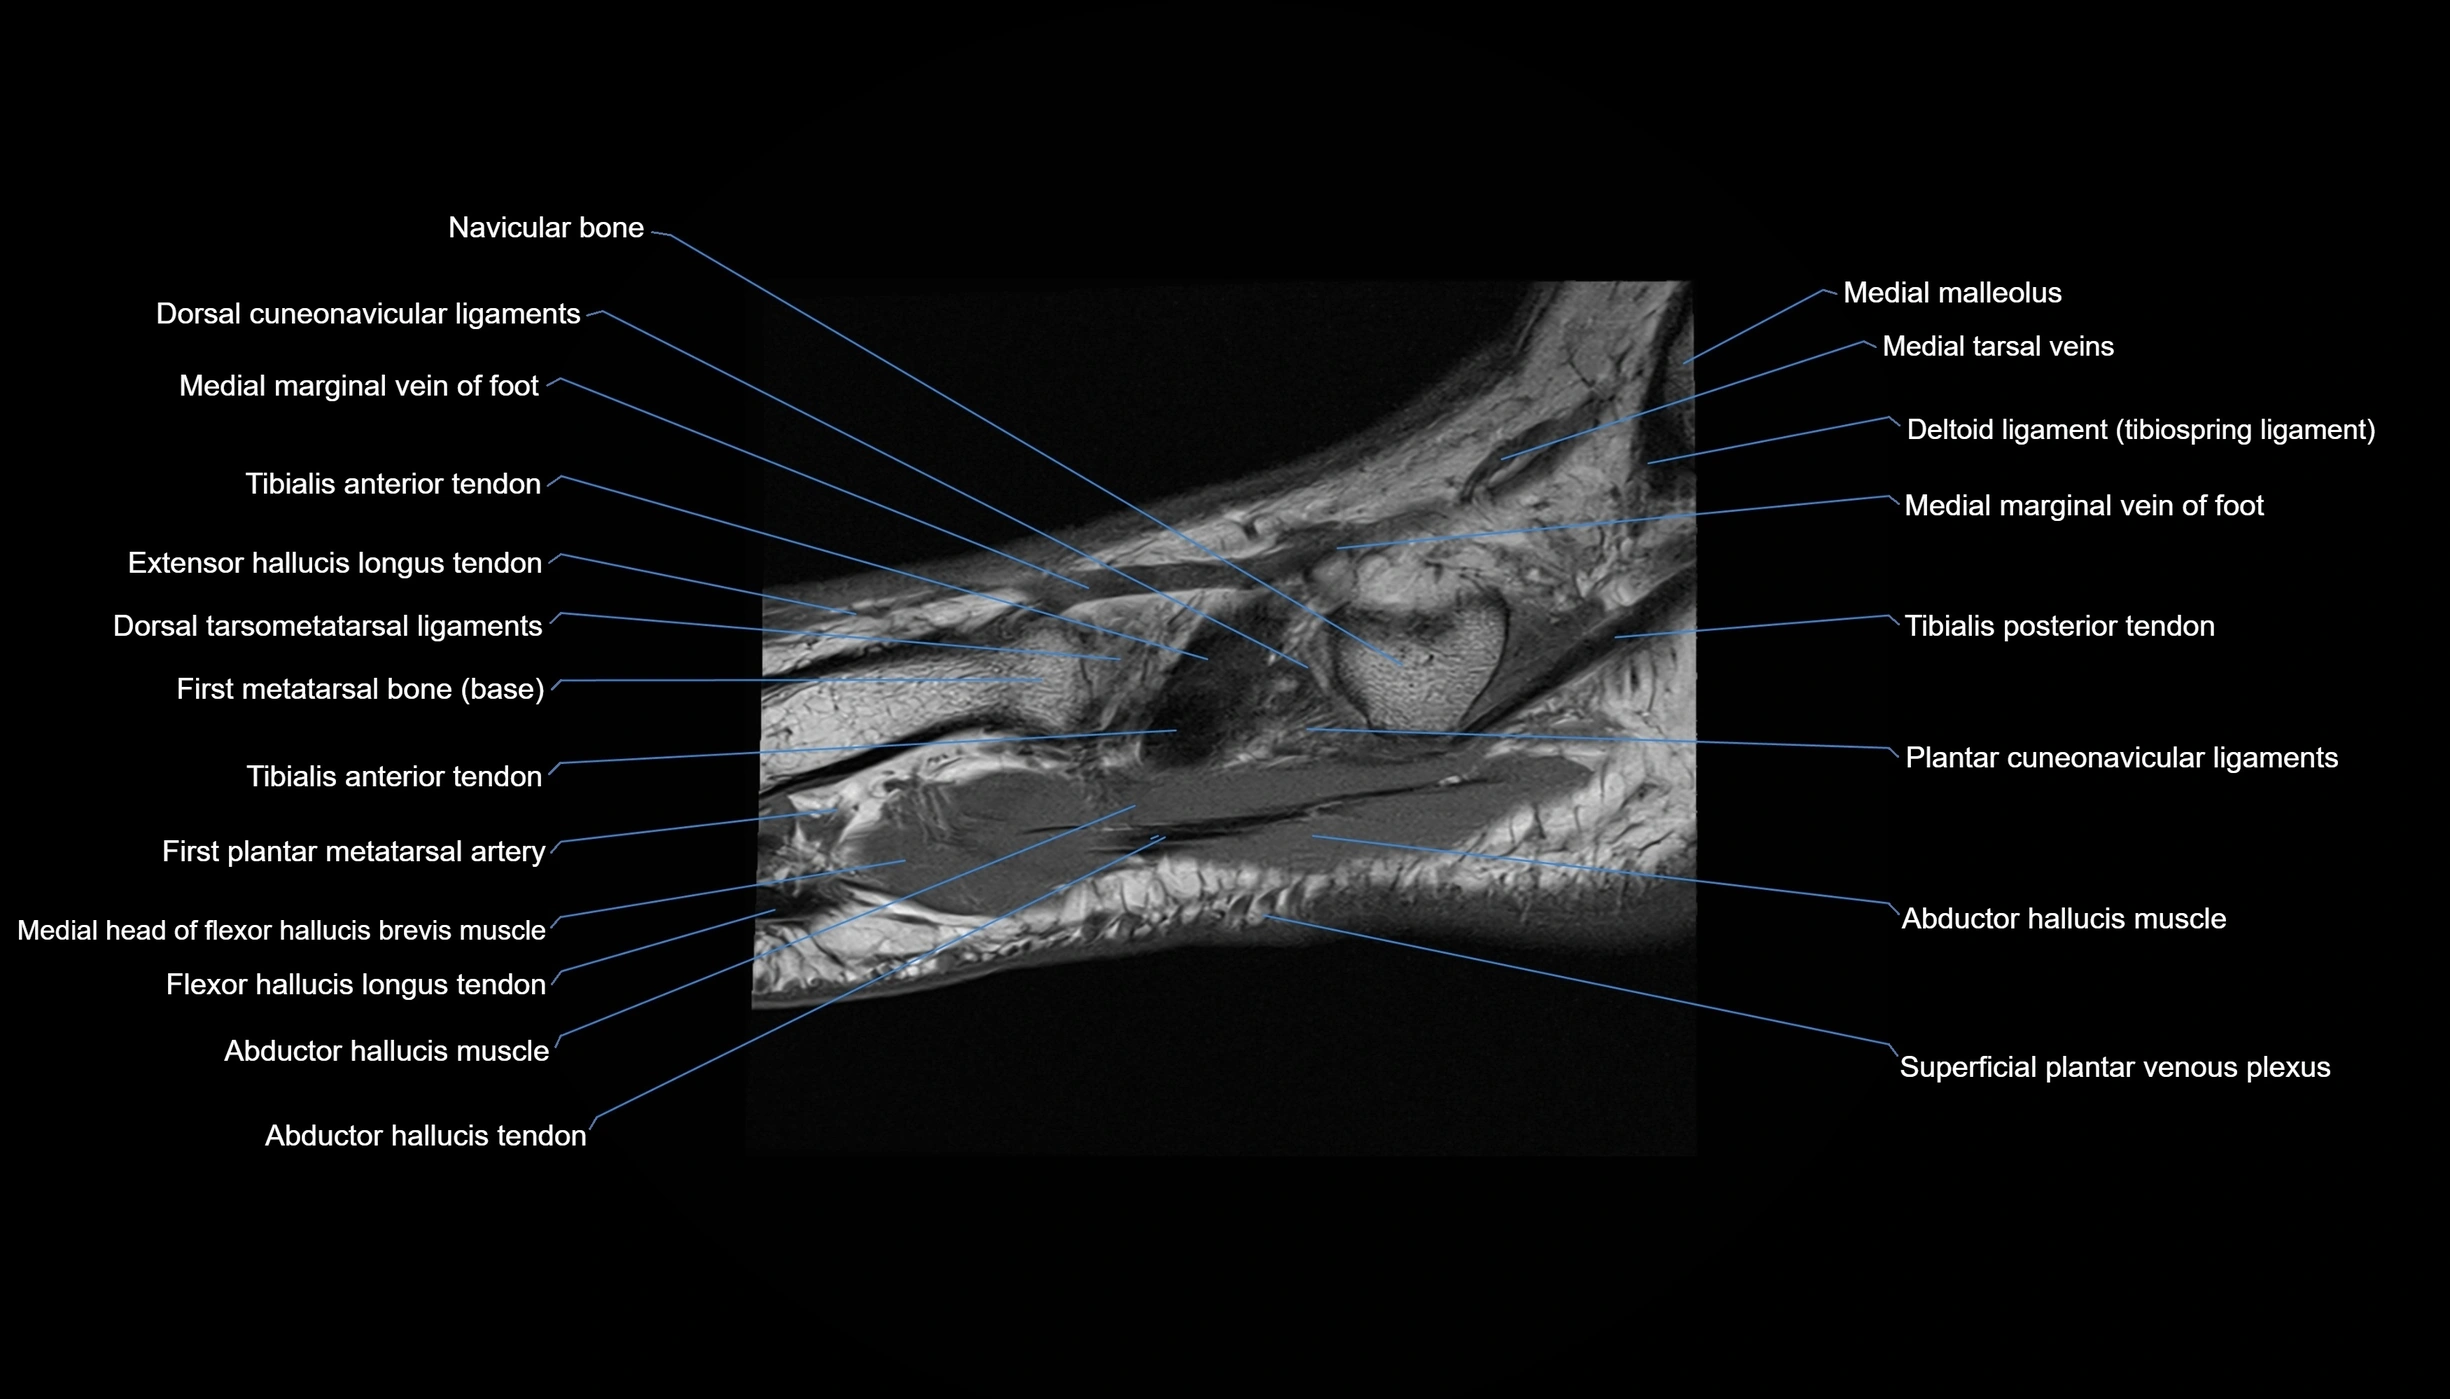

MRI image